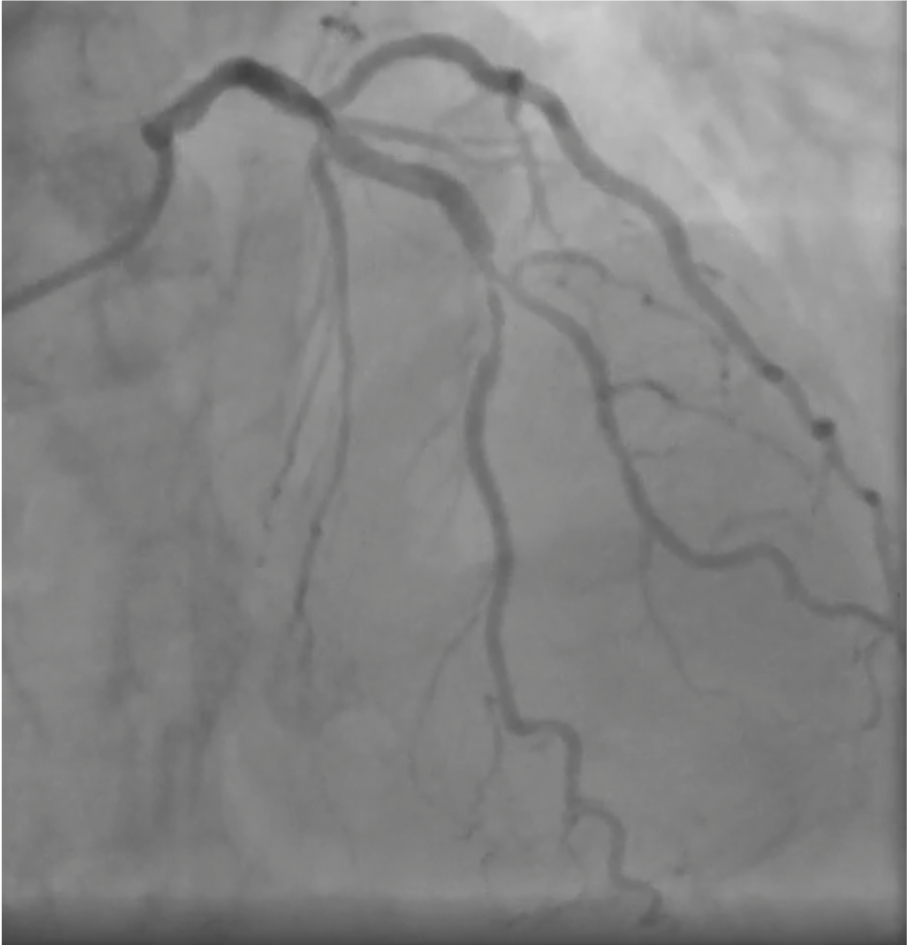

Coronary angiography via left distal radial access revealed two-vessel coronary artery disease. A true LAD–Diagonal bifurcation lesion (Medina 1.1.1) was noted, with 80% stenosis in the LAD middle segment and 80% stenosis at the D2 ostium. The proximal RCA showed critical 99% stenosis. Resting coronary physiologic indices showed: LAD-O 0.99, LAD-M 0.73, LAD-D2 0.80